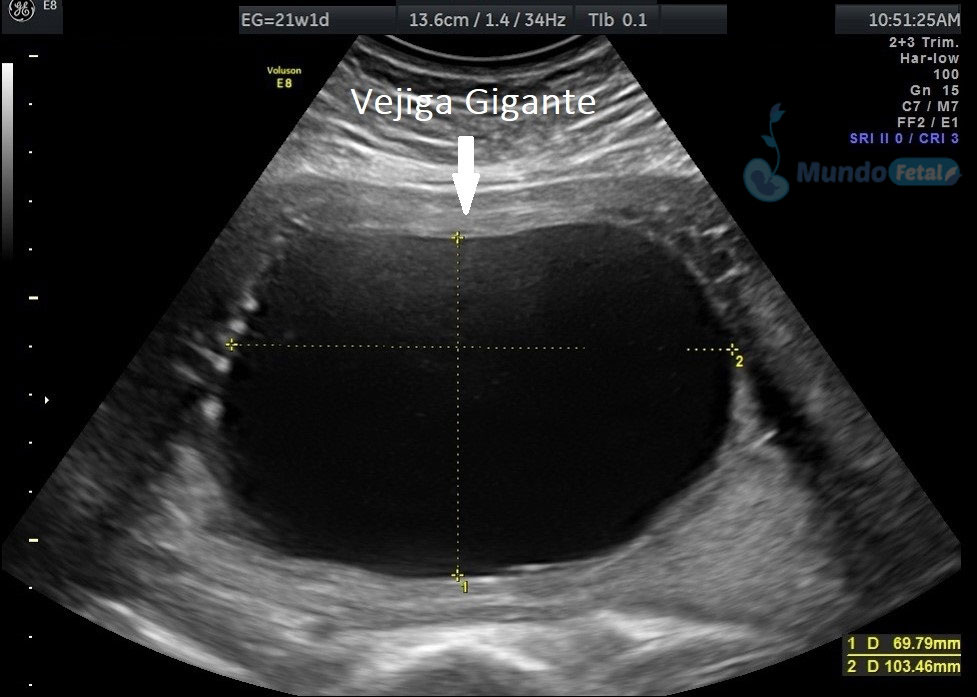

Ultrasonido Nivel II, Patología Fetal

Estudio llevado a cabo en todo bebe, en quien se haya detectado alguna alteración anatómica o marcador de riesgo, valorando todos sus órganos, aparatos y sistemas, de manera específica y detallada.